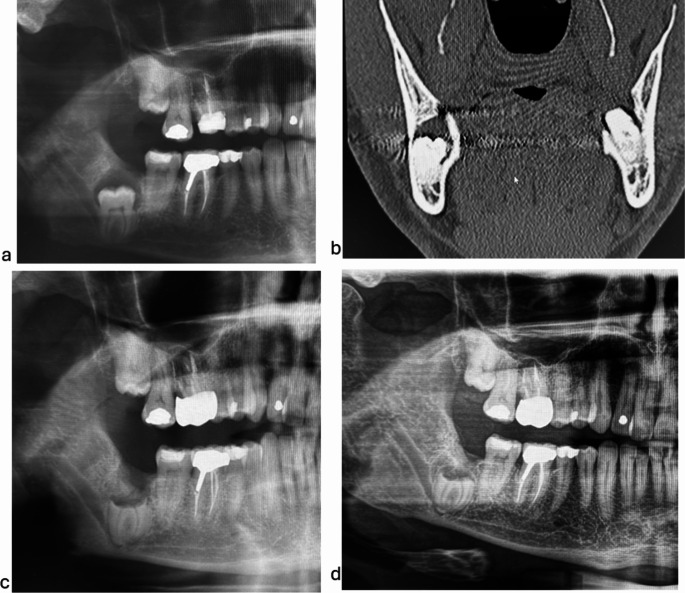

Purpose: Coronectomy is a valuable treatment proven safe for non-pathological mandibular third molars with an increased risk of inferior alveolar nerve injury. Coronectomy may also be useful for mandibular third molars with dentigerous cysts and caries, but this is not commonly performed due to the lack of well-designed, evidence-based studies. Here, we aim to investigate the safety of coronectomy for mandibular third molars with caries and dentigerous cysts.

Methods: One hundred fifteen patients with an impacted mandibular third molar with a dentigerous cyst or caries underwent coronectomy or complete removal and received follow-up with clinical and radiographical examinations. We statistically compared the presence of postoperative complications after coronectomy versus complete removal.

Results: Data from 121 molars were available for analysis. The results revealed no significant difference in the occurrence of postoperative complications (including persistent pain, inferior alveolar nerve injury, infection, alveolar osteitis, excessive bleeding, and the need for retreatment) between coronectomy and complete removal. Additionally, the incidence of postoperative complications was not related to any analyzed patient- or molar-related factors, including age, gender, health status, smoking, caries, dentigerous cyst extent, and impaction degree.

Conclusion: For pathological impacted mandibular third molars with dentigerous cysts and caries, coronectomy exhibited both short-term and long-term safety, showing no significant difference in postoperative complications compared to total removal. Our results suggest that coronectomy can be indicated for pathological mandibular third molars with proximity to the inferior alveolar nerve.